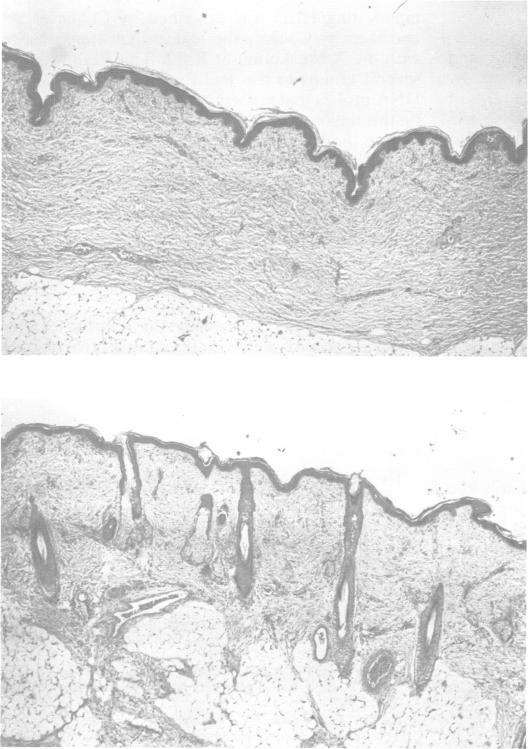

Hypohidrotic ectodermal dysplasia.

J Med Genet. 1987 Nov;24(11):659-63. doi: 10.1136/jmg.24.11.659.